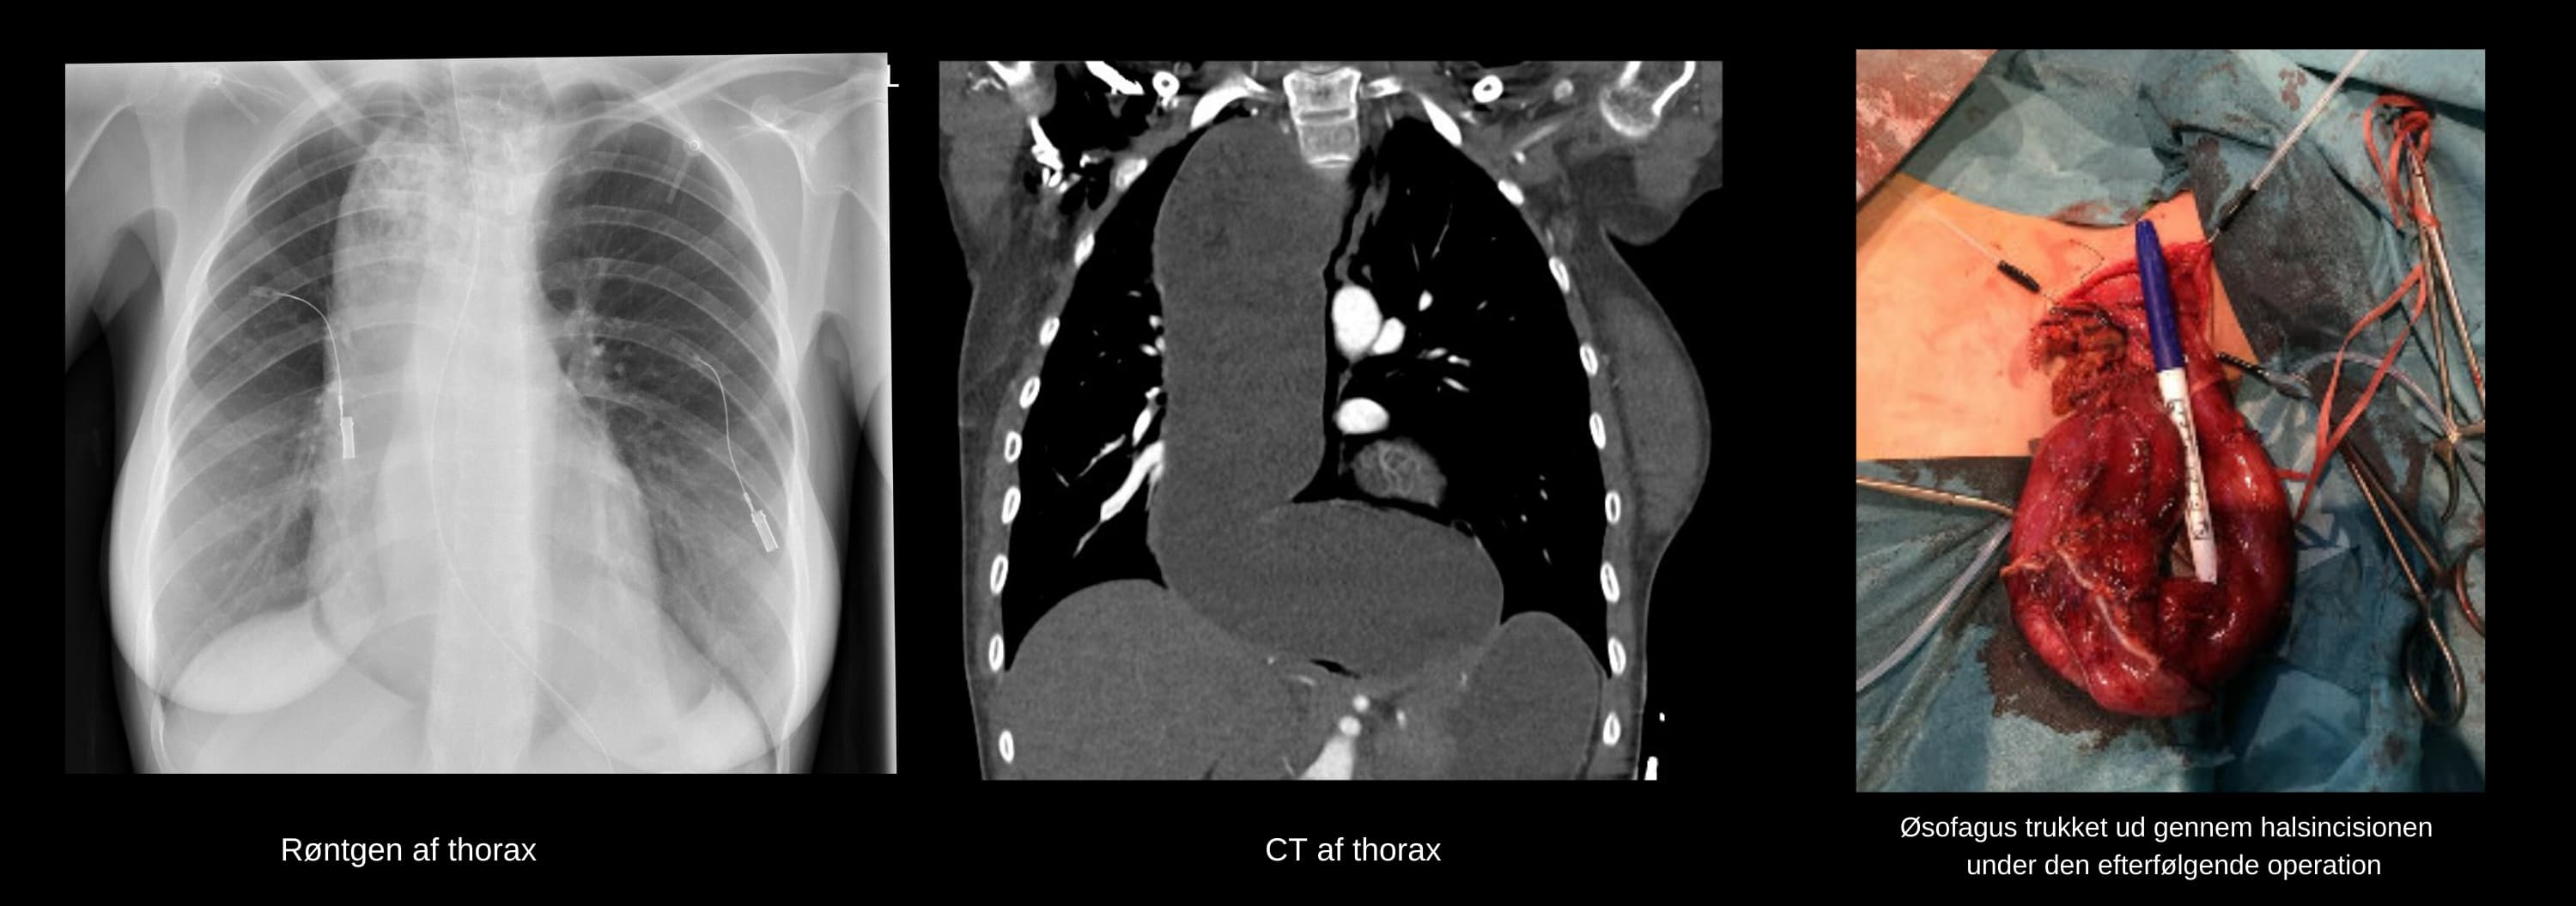

En 22-årig kvinde fødte sit første barn ukompliceret vaginalt, men fik umiddelbart herefter akut respirationsbesvær med påskyndet stridorøs vejrtrækning. En røntgenundersøgelse af thorax viser breddeforøget mediastinum. Der blev foretaget akut CT, der viste massivt dilateret væskefyldt øsofagus med tryk på trachea og højre hovedbronchus, hvilket var foreneligt med akalasi. Patienten blev overflyttet til et intensivafsnit, hvor den respiratoriske tilstand bedredes.